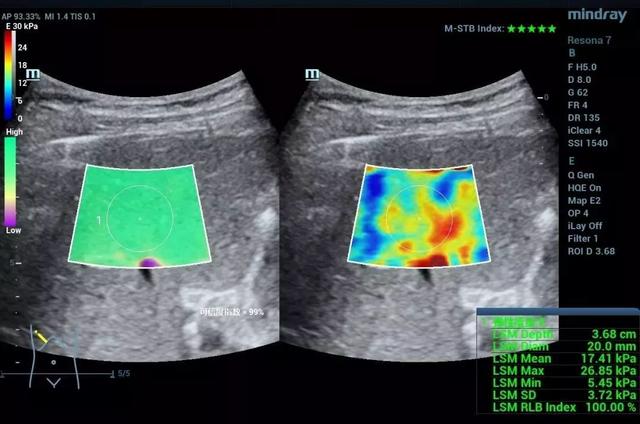

3. 二维剪切波弹性成像(2D- SWE/STE)

接着,剪切波弹性成像继续飞速发展。每个厂家也用不同的发射激励和接收信息的办法实现了二维剪切波弹性成像。

迈瑞是怎么做的

迈瑞采用队列式发射及超宽波速追踪成像。利用医学超声功率范围内的聚焦超声波束的辐射力,在生物黏性组织局部区域内产生剪切波。超声系统追踪剪切波的传播速度,持续地追踪和记录ROI内剪切波引起的组织的位移改变。最终,获得剪切波的传播速度和推导出组织的弹性模量。剪切波可以在不同的位置依次产生并传播,系统获取每个位置的剪切波速度,进而形成一幅剪切波弹性图像。STE可以以高达每帧10KHz的速度,有效地探测剪切波的信号。声辐射力产生的剪切波的幅度很微弱,通常只有几微米到几十微米。在剪切波传播过程中,STE技术通过微调接收波束的位置,使得超声波束的能量尽可能的集中,从而提高接收信号的质量。

作为一种无创的能够反应组织硬度的功能性成像方法。目前剪切波弹性成像的研究已经涉及肝脏、甲状腺、乳腺、胃肠道、肌骨等方方面面,对于弥漫性病变的分级、局灶性病变的鉴别诊断、疾病的监测及随访等都有重要的意义。例如诊断肝脏纤维化的分期,从F1-F4的图像中,我们发现,尽管二维声像图差别不大,但当纤维化程度增高时,肝脏杨氏模量也增高了,也就是说肝脏“变硬”了。可见,超声发展到这里,不但有形态学上的灰阶超声,血流动力学上的彩色多普勒超声,还有机械力学上的弹性超声。